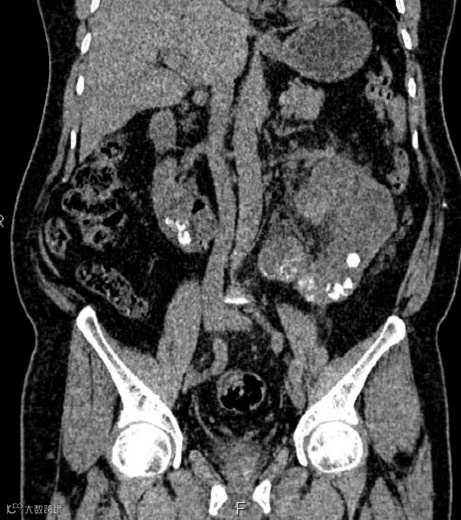

男,55岁,马蹄肾合并双肾多发结石,右肾积水(泌尿系气泡为导尿术后改变)。